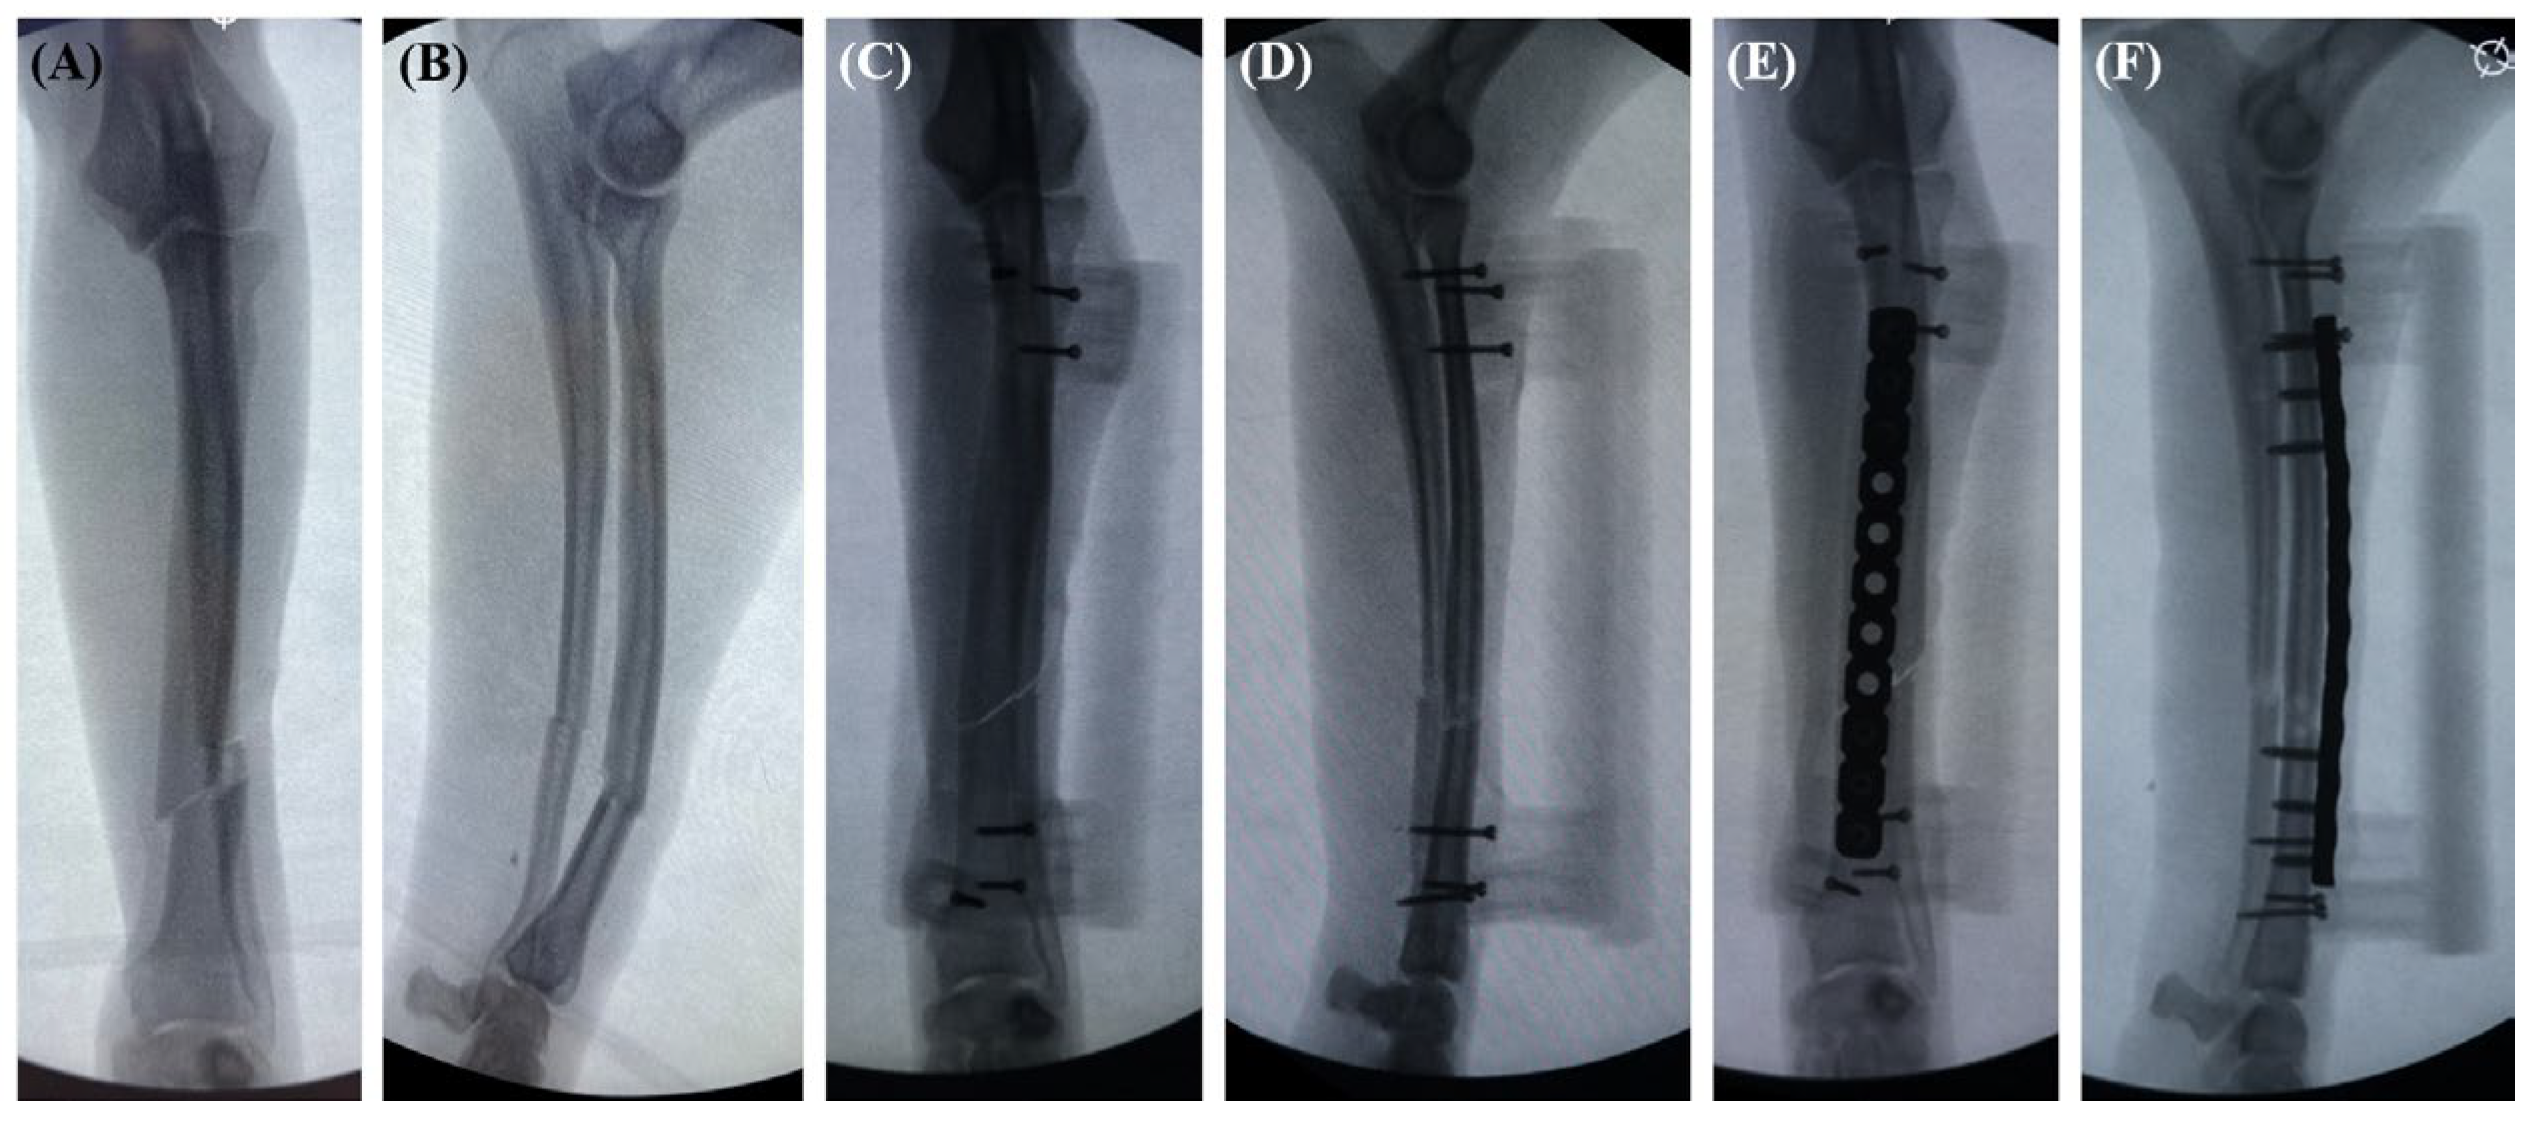

2.4. Surgical Procedure

3. Results